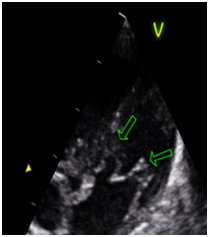

Usually they associated with aortic aneurysm, bicuspid aortic valve, aortic coarctation, subaortic stenosis, patent ductus arteriosus, abnormal interatrial and interventricular septum. They may evolve failure and / or mitral stenosis. (Figures 1–4)

Figure 1 Parasternal short axis.